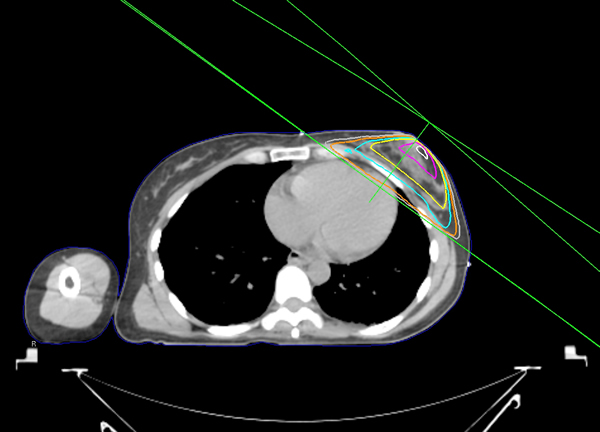

Treatment fields for Breast cancer are typically 2 tangent fields. The fields are angled slightly so there is a non-divergent border on the posterior side. This will help reduce unnecessary dose to the lung, heart, contralateral breast and other uninvolved areas. It is important to contour heart and lungs accurately so the Physician may see the dose to those structures and adjust fields accordingly, if necessary.